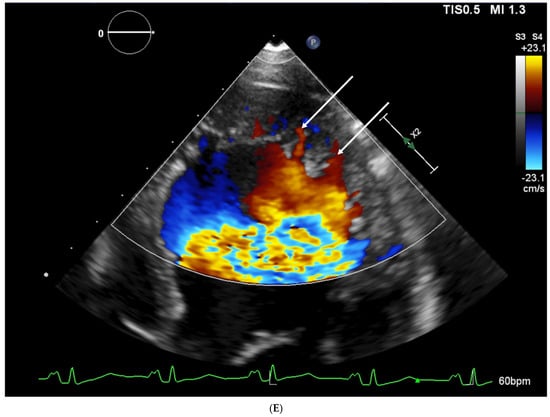

4.1. Echocardiography

| Chin [3] | ECHO | The ratio of the distance from the deepest trabecular recess to the epicardial surface (X) and the distance from the tip of the trabeculation to the epicardial surface (Y) | Long axis, end diastole | X/Y ≤ 0.5 |

| Stöllberger [47] | ECHO | Ratio of compacted and non-compacted endocardium. Presence of at least 3 trabeculations protruding in the left ventricle apically from papillary muscle, presence of the blood flow between trabeculations. | Four chamber, end diastole | NC/C > 2 |

| Jenni [33] | ECHO | Ratio of compacted and non-compacted endocardium. Absence of coexisting cardiac abnormalities, the presence of deep trabeculations, which are filled with blood | Short axis, end systole | NC/C ≥ 2 |